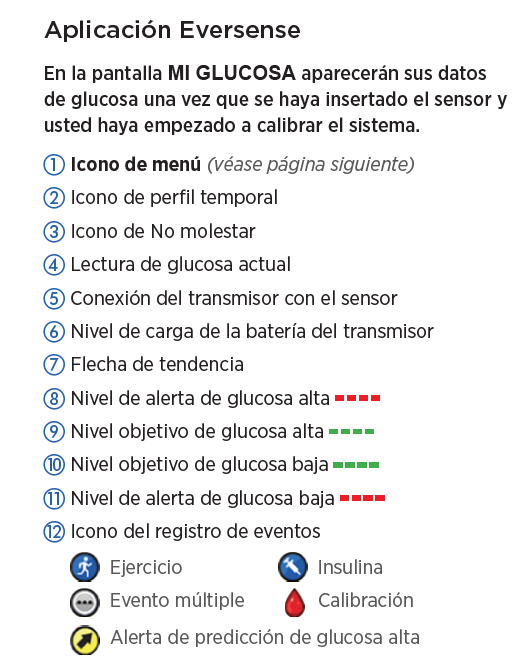

Primero, revisemos la pantalla de inicio

Mi glucosa en la aplicación para móvil Eversense®.

PANTALLA DE INICIO MI GLUCOSA

Cuando abre la aplicación para móvil Eversense®,

se muestran principalmente su nivel

de glucosa actual y una flecha de tendencia.

En la parte superior derecha, puede ver

la intensidad de la conexión entre el transmisor y el sensor, y la carga de la batería que tiene

el transmisor.

PANTALLA DE INICIO MI GLUCOSA

Si ha activado la función No molestar o Perfil temporal, aparecerán los iconos correspondientes

en la parte superior izquierda.

PANTALLA DE INICIO MI GLUCOSA

Y, en la parte inferior, se encuentra el gráfico de tendencia de la glucosa.

Las líneas discontinuas rojas indican los niveles de alerta de glucosa alta y baja, y las líneas discontinuas verdes indican el intervalo objetivo.

Todos los eventos que introduzca en la aplicación (como una calibración, comida, ejercicio

o insulina) o las alertas que reciba, se mostrarán en el gráfico de tendencia con un icono.

PANTALLA DE INICIO MI GLUCOSA

Si ha activado la función No molestar o Perfil temporal, aparecerán los iconos correspondientes en la parte superior izquierda.

Puede consultar la sección Utilizar la aplicación para móvil en la Guía de consulta rápida del sistema de MCG Eversense® E3 en cualquier momento.